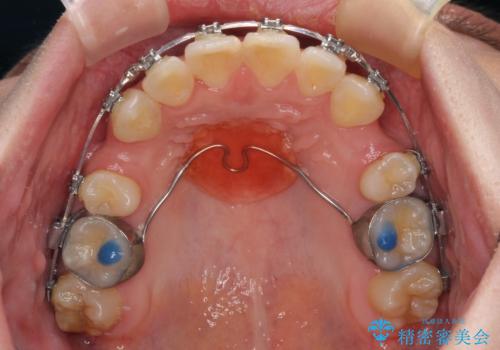

- 矯正装置

- メタルブラケット

第二小臼歯抜歯の治療となったため、やや時間はかかりましたが、概ね予想通りの期間で治療を終えることができました。